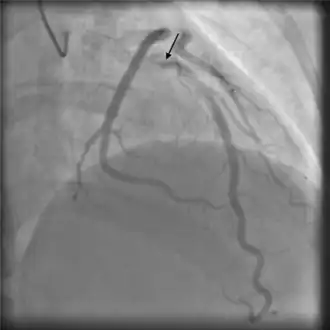

Angiography

Angiographic appearances of SCAD fall into three categories.[13] Type 1 lesions appear as classic angiographic dissections, with a false lumen distinct from the true lumen. These are the easiest to identify as SCAD clinically, though relatively uncommon.[13] Type 2 lesions - the most common subtype of SCAD - appear as a long, smooth narrowing of the vessel without a distinctly visible false and true lumen.[6] Type 3 lesions appear similar to atherosclerotic lesions and are difficult to confirm as SCAD through angiography alone,[16] possibly requiring the use of intracoronary imaging.

-

Angiographic image-contrast was seen to swirl and stay longer than usual, consistent with self-limiting spontaneous coronary artery dissection -